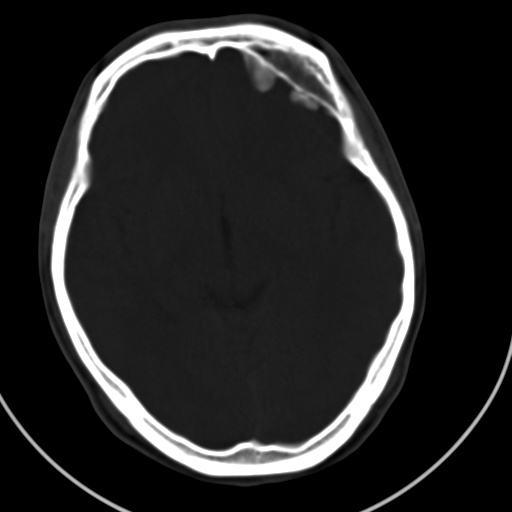

标题: CT21939:男20岁,外伤一年后,现头疼. [打印本页]

标题: CT21939:男20岁,外伤一年后,现头疼.

凹陷的很像颅骨内板。

如果是骨折,外板正常内板这么明显凹陷,请问这样的骨折是怎样形成的?形成的机理是什么?有没有可能形成?

左侧额部硬膜外血肿机化、骨化。

左侧额部硬膜外血肿机化、骨化